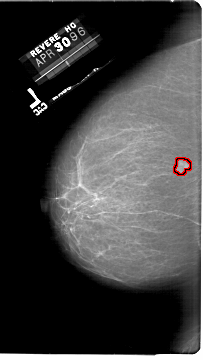

FILE: A_1865_1.LEFT_CC.OVERLAY

TOTAL_ABNORMALITIES 1

ABNORMALITY 1

LESION_TYPE MASS SHAPE LOBULATED MARGINS OBSCURED

ASSESSMENT 4

SUBTLETY 4

PATHOLOGY BENIGN

TOTAL_OUTLINES 1

BOUNDARY